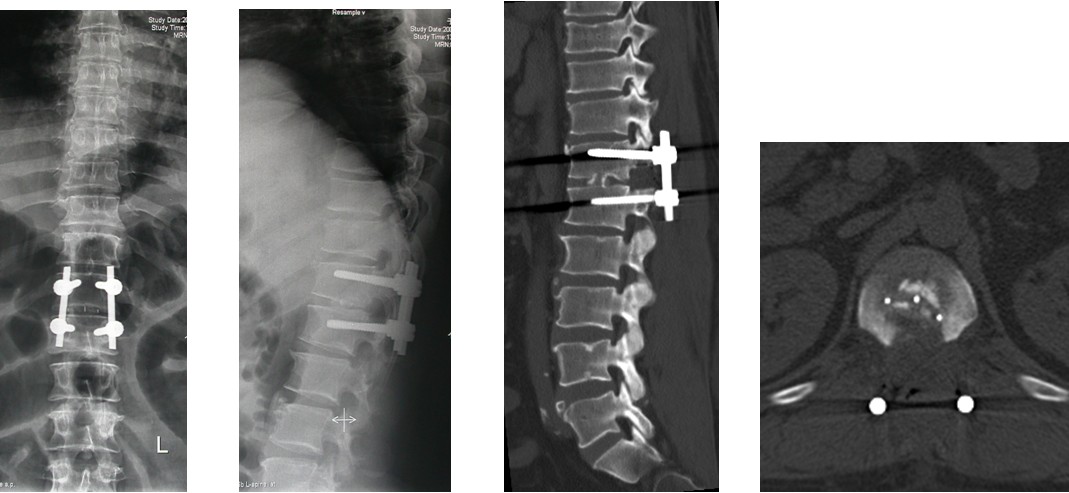

4. 典型病例:病例1,患者男性,40岁,司机。主因胸腰背部疼痛3年,肛周麻木、性功能减退并伴双足下垂2年,症状加重且二便肥力、无法工作1年入院。入院查体:一般情况良好,体胖、体重105kg。步态不稳,步行缓慢。胸腰段脊柱背部轻压痛,无放射。双侧股四头肌力IV级,双侧胫前肌力I级,双侧足下垂。鞍区感觉减退,无病理征。双侧跟、膝腱反射消失。血化验检查正常。X线平片显示T12~L1椎间隙明显变窄。CT显示T12~L1椎间盘突出并椎体后缘离断。MRI显示T12~L1椎间盘呈中央型突出,椎管狭窄,脊髓明显受压变形。入院诊断:T12~L1椎间盘突出症伴椎体后缘离断,马尾神经损害。术前检查完成后,在气管插管全麻下行上述经极外侧入路T12~L1椎间盘切除手术治疗,整个手术过程顺利,无术中及术后并发症发生,术后1周顺利出院。出院时,其双侧股四头肌、胫前肌肌力已分别恢复至V级和III级;鞍区感觉减退亦有明显好转。术后显示T12~L1突出之椎间盘及离断之椎体后缘已被完全切除,椎间融合器及椎弓根螺钉位置佳,脊柱局部生理曲度良好(图2a~2l)。病例2,女性患者,59岁。主因间歇性跛行,双下肢无力3年入院。入院诊断:T11椎体后上缘骨软骨瘤。以与病例1相同的术式行椎体骨软骨瘤的彻底切除(图3a~3l),无手术并发症发生,术后患者下肢症状明显改善。

图2a~2d. 典型病例1患者术前CT, MRI均显示为T12~L1椎间盘突出合并椎体后缘离断, 致椎管狭窄, 脊髓明显受压

图2e~2h. 典型病例1手术中情况: 关节突关节切除, 椎间盘切除, 椎间融合器植入及椎弓根固定

图2i~2l. 典型病例1患者术后X线片, CT显示突出之椎间盘及离断的椎体后缘已被彻底切除, 内固定和椎替间融合器位置良好.